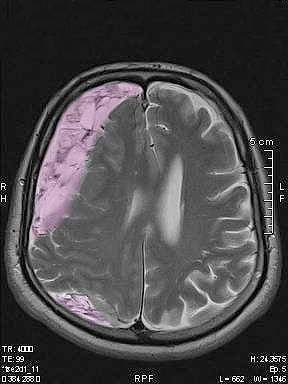

Αξονική ή μαγνητική τομογραφία εγκεφάλου. Σε ορισμένες περιπτώσεις τα χρόνια υποσκληρίδια αιματώματα μπορεί έχουν την ίδια πυκνότητα στην απεικόνιση με το εγκεφαλικό παρέγχυμα ή να βρίσκονται ακόμη σε πρώϊμο στάδιο ανάπτυξης όσον αφορά στο μέγεθος και τη σύσταση, και αυτό μπορεί να καταστήσει την διάγνωση πιο δύσκολη.